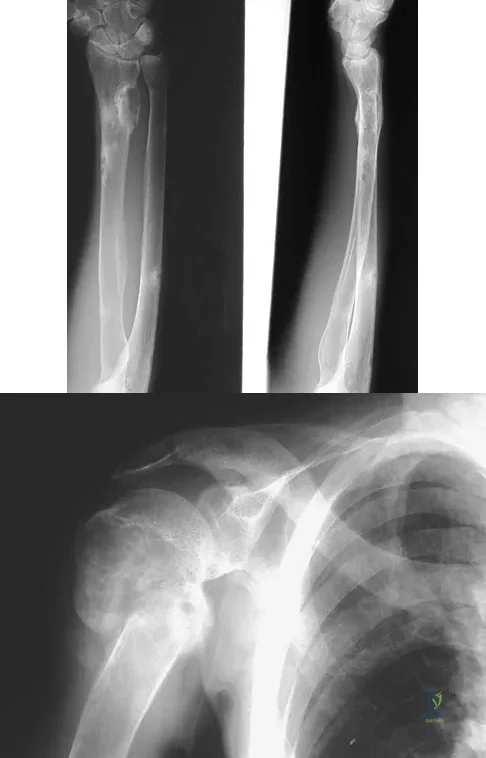

A 29-year-old woman reports shoulder pain after sustaining a minor fall 6 weeks ago. She has a history of celiac sprue. Radiographs of the forearm and shoulder are shown in Figures 53a and 53b. Which of the following serum abnormalities would be expected?

Explanation